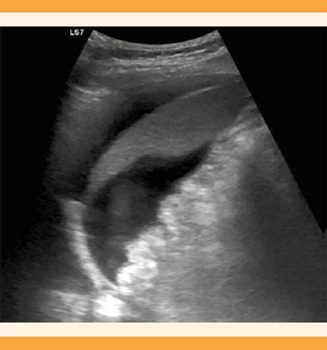

Catorce días después de la transferencia, la paciente acudió a Urgencias debido a dolor costal derecho y disnea, asociado con tos no productiva. Durante el examen físico se advirtió una disminución de ruidos ventilatorios en el hemitórax derecho. La tensión arterial fue de 146-69 mmHg, el pulso 108 lpm, la temperatura de 36.8 oC, la frecuencia respiratoria de 30 rpm y la saturación de oxígeno del 94%. La ecografía torácica tomada en Urgencias objetivó un derrame pleural derecho, con atelectasia del pulmón subyacente del que se evacuaron, de manera ecoguiada, 1300 cc de líquido seroso, que se remitieron para estudio con reporte de trasudado (Figura 1). La ecografía abdominal mostró escaso líquido libre y a los ovarios de aspecto hiperestimulado, de 9 cm de diámetro máximo (Figura 2). El pH de la sangre venosa fue de 7.41, pCO2 41.9 mmHg, pO2 31.1 mmHg. La concentración de hemoglobina fue de 12.4 g/dL, leucocitosis de 19.41 x 10^3/µL, hematocrito del 38%, recuento de plaquetas 395,000/mm3, creatinina 0.89 mg/dL, sodio 139 mEq/L y potasio 3,9 mEq/L.